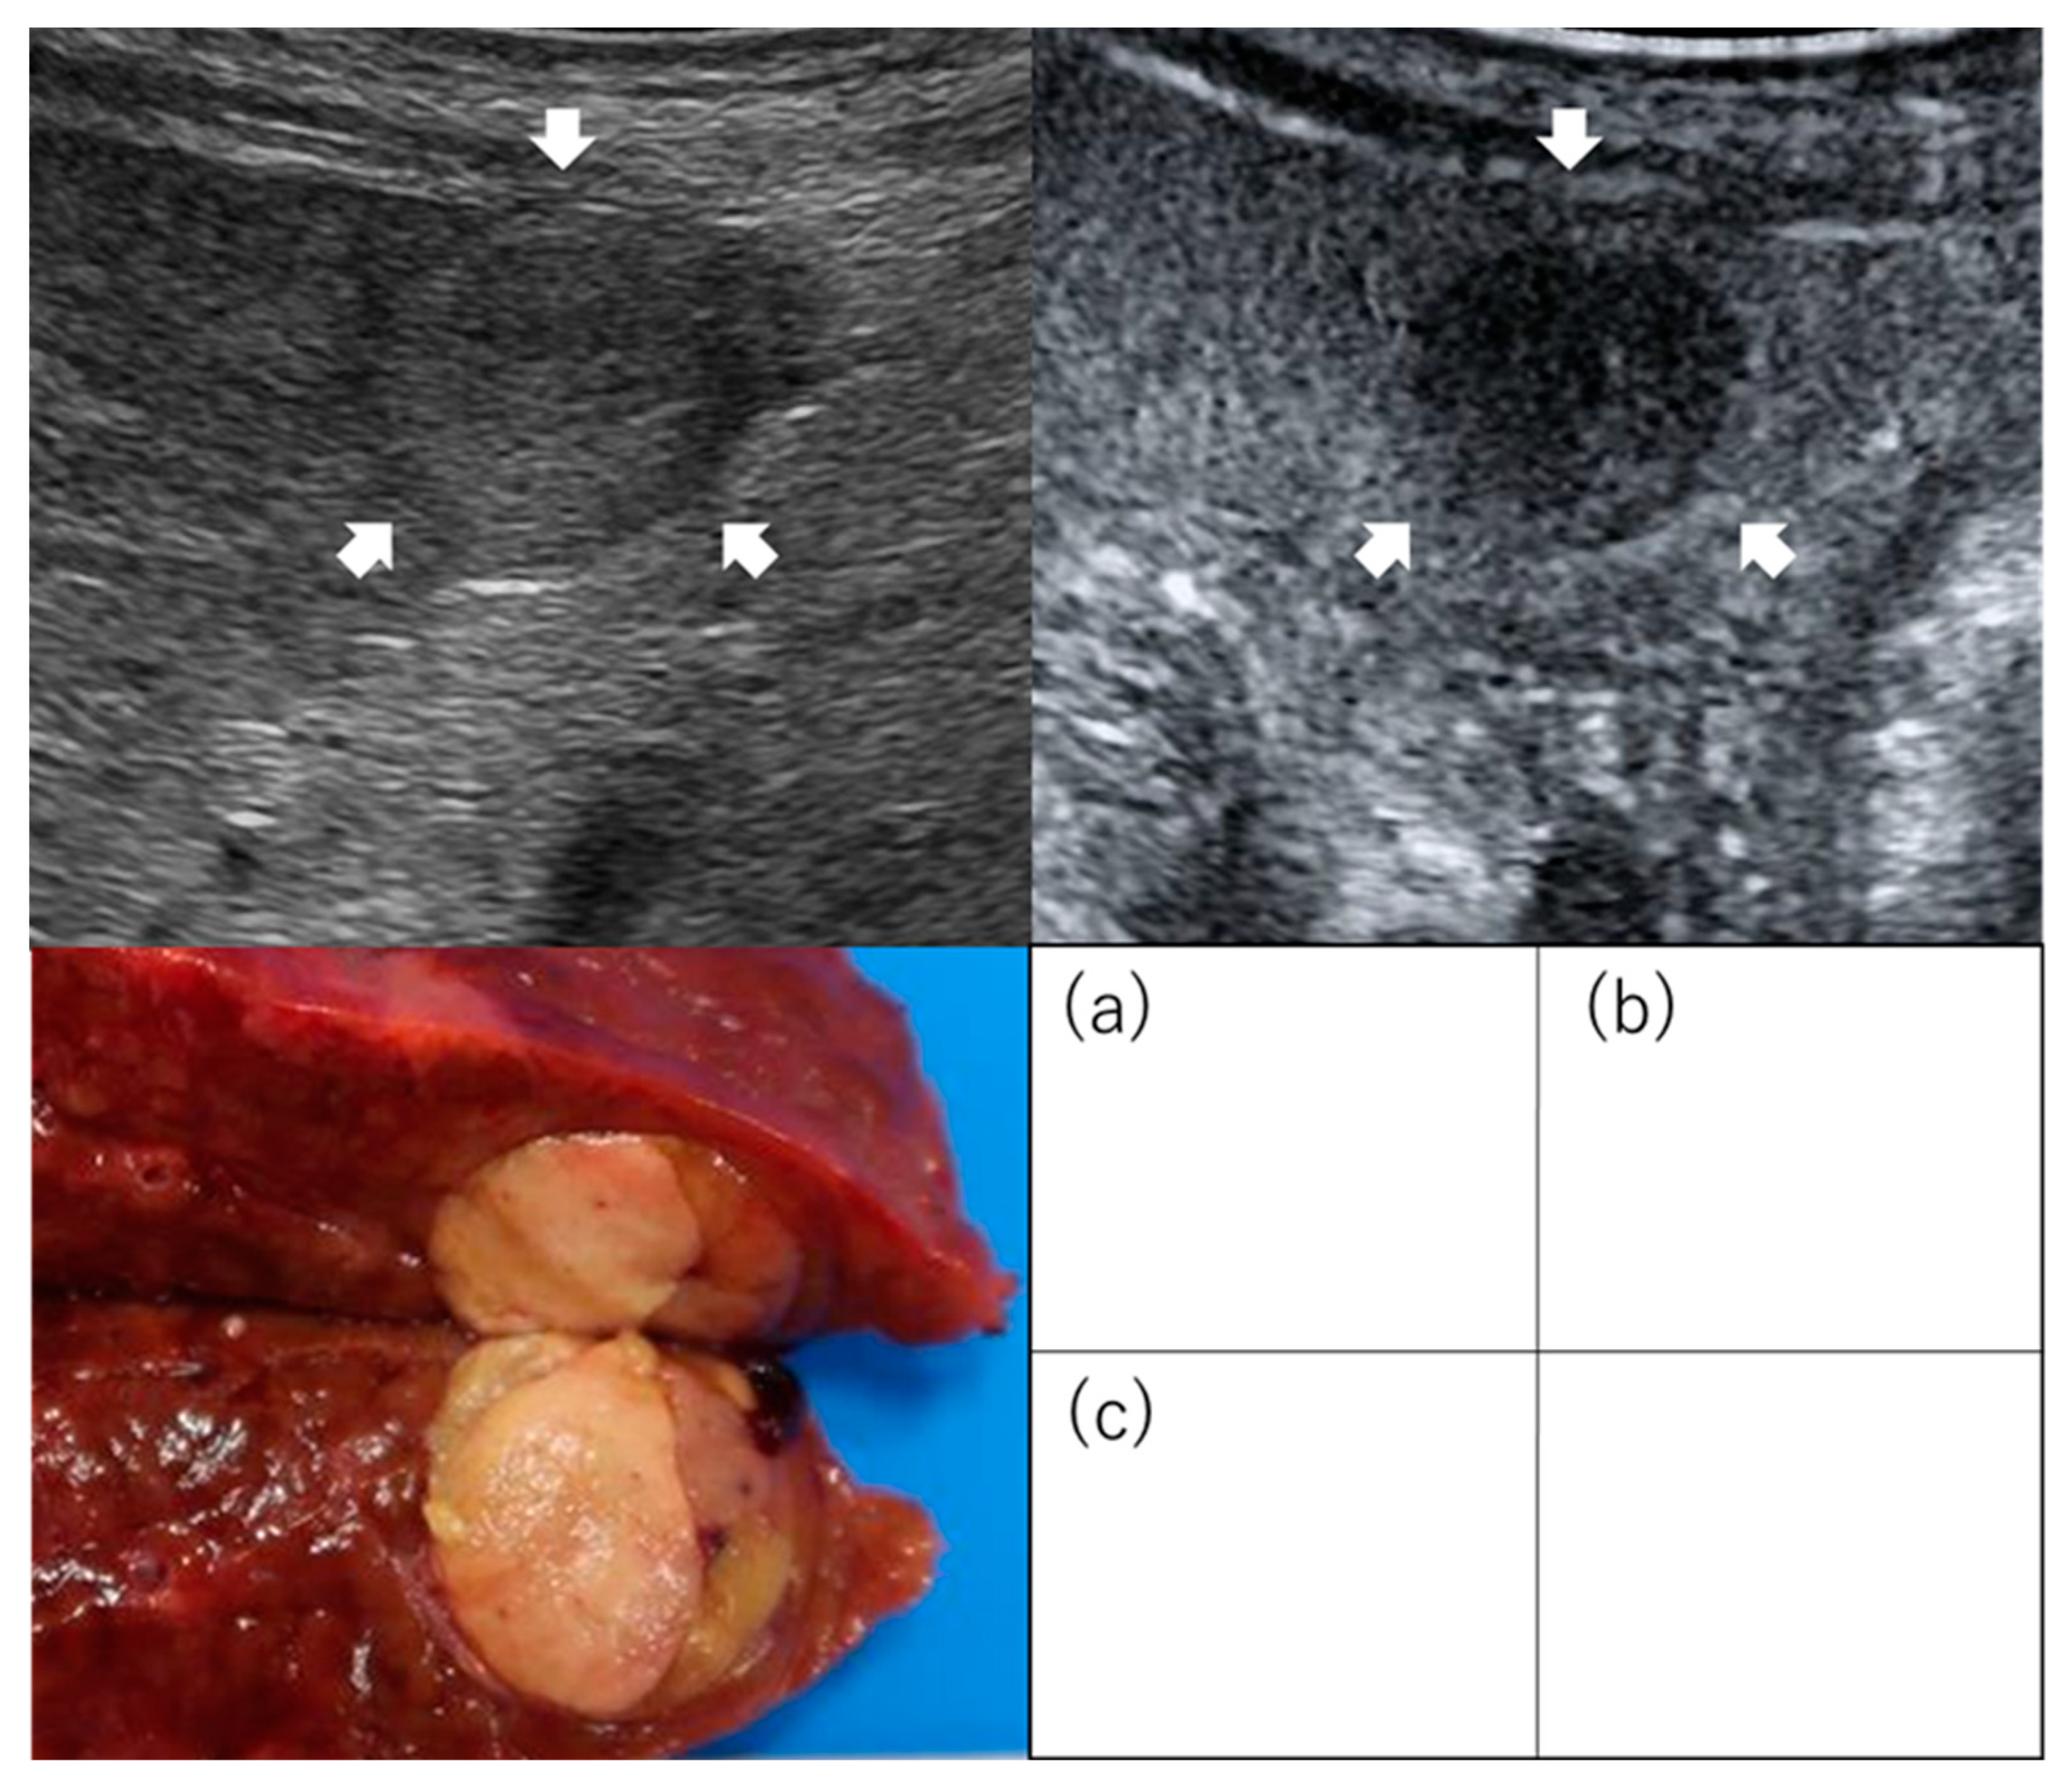

2.1. Gross Classification

- Hatanaka, K.; Chung, H.; Kudo, M.; Haji, S.; Minami, Y.; Maekawa, K.; Hayaishi, S.; Nagai, T.; Takita, M.; Kudo, K.; et al. Usefulness of the post-vascular phase of contrast-enhanced ultrasonography with sonazoid in the evaluation of gross types of hepatocellular carcinoma. Oncology 2010, 78 (Suppl. S1), 53–59. [Google Scholar] [CrossRef]

| Hatanaka et al. [28] | 29 | Solitary and ≤5 cm ≤3 tumors and ≤3 cm | LR | Gross type (SN type or non-SN type) | Sensitivity, 96%; specificity, 80%; accuracy, 90% |

| Li et al. [29] | 31 | Early stage | LR | Microvascular invasion | Non-SN type in the post-vascular phase image was an independent predictor of microvascular invasion (OR, 30.51; 95% CI, 2.335–398.731, p = 0.009). Sensitivity, 93.3%; specificity, 81.3%; positive predictive value, 82.4%; negative predictive value, 92.9% |

| Nuta et al. [30] | 73 | Solitary and ≤5 cm | LR | Gross type (SN type or non-SN type) Outcome (recurrence) | In the post-vascular phase, predictability for high-grade malignant potential was as follows: sensitivity was 93%, specificity was 85%, positive predictive value was 97%, negative predictive value was 73%, and accuracy was 92%. Irregular defect pattern was one of the independent factors for metastatic recurrence (HR, 4.388; 95% CI, 1.008–19.089; p = 0.049). |